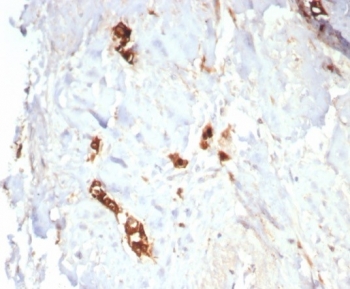

Mammaglobin Antibody Recombinant Rabbit MAb MGB/7980R immunohistochemistry of human lactating breast tissue. FFPE human lactating breast tissue was stained with Mammaglobin Antibody Recombinant Rabbit MAb MGB/7980R. HRP-DAB brown chromogenic signal highlights cytoplasmic staining in secretory epithelial cells of mammary glandular structures, consistent with expression of Mammaglobin A / SCGB2A2 in lactating breast epithelium, while surrounding stromal cells show minimal staining. Heat-induced epitope retrieval was performed by boiling tissue sections in pH 9 10mM Tris with 1mM EDTA for 20 minutes followed by cooling prior to staining.